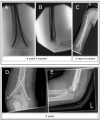

To assess changes in treatment modalities for supracondylar humerus fractures (SCHFs) at a large pediatric university hospital, we analyzed patient data from 2014 to 2022. A total of 233 SCHFs treated surgically at our hospital were included. To evaluate postoperative outcome and quality of life, DASH and EuroQol-5D-Y questionnaires were sent to patients. In addition to a significant fluctuation in fracture severity, we found an increase in training interventions (more surgeries were performed by trainees) and a significant decrease in surgery times after 2016. From 2020, there was a significant shift in the type of surgical method away from closed reduction with elastic stable intramedullary nailing (ESIN) and towards closed reduction and crossed K-wire osteosynthesis (CRK). Surgeries performed in the morning and evening hours increased, while those performed in the afternoon and after midnight decreased. After a mean follow-up of 4 years, there was no difference in elbow function between ESIN and open reduction and K-wires (ORK). Treatment with ESIN was equivalent to ORK in terms of function, at least in the medium-term follow-up. In summary, the combination of shifting treatment from SCHF to daytime hours, increasing trainee participation and using cross K-wire fixation instead of ESIN had no negative impact on surgery times. In our setting, these measures have reduced resource utilization and increased efficiency without compromising patient care.